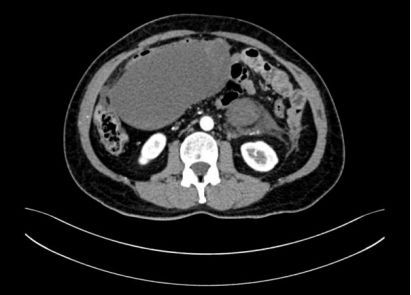

腹盆腔内见巨大混杂密度影,形态欠规则,最大截面约91×206mm,增强后病灶内实性成分可见强化,囊性成分未见强化。后腹膜未见明显肿大淋巴结,盆腔内见少许积液。提示:腹盆腔内巨大占位。

图1:CT图像表现